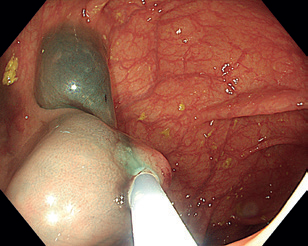

Obr. 3 Stopkatý polyp 0‑Ip zobrazený metodou Narrow Band Imaging.Endoskopická polypektomie (EPE) představuje základní a nejčastěji využívanou terapeutickou proceduru v oblasti gastrointestinální endoskopie. Princip EPE spočívá v naložení polypektomické kličky na stopku stopkatého polypu (0‑Ip), která je tvořena zdravou sliznicí a submukózou, následně je tato stopka přerušena kombinací mechanické síly při uzavření smyčky a elektrického koagulačního proudu (technika známá jako „hot snare“) (obr. 3–5). U rizikových polypů (šíře stopky nad 10 mm či velikost polypu nad 20 mm) se pro minimalizaci rizika krvácení doporučuje před resekcí stopku infiltrovat roztokem adrenalinu, popř. na stopku naložit endoklipy nebo použít odnímatelnou smyčku, známou též jako „endo­loop“, která po resekci polypu zůstává na stopce (obr. 6). EPE se často využívá i pro resekci malých plochých nebo přisedlých lézí (0‑IIa, 0‑Is) s průměrem ≤ 10 mm (obr. 7), a to obvykle pouze v mechanickém režimu bez využití elektrické koagulace (technika známá jako „cold snare“). Tato metoda snižuje riziko pozdějšího krvácení a vzniku koagulačního syndromu. „Resekce“ diminutivních lézí pomocí biop­tic­kých kleští, běžně používaná v minulosti, byla do značné míry opuštěna pro riziko inkompletní resekce a nahrazena právě „cold snare“ polypektomií. Klešťovou resekci je nadále možno použít jen u lézí do velikosti 3 mm. Použití elektrokoagulačních kleští („hot forceps”) se obecně nedoporučuje.

Obr. 5 Extrakce resekátu stopkatého polypu.EMR zahrnuje několik technik. Nejběžnější je technika „lift and cut“, při které se provádí submukózní injekce různých roztoků vedoucí ke zvednutí léze s následným uchopením a odstraněním kličkou (obr. 8–11). Submukózní injekce může obsahovat fyziologický roztok, glukózu a glycerol, zředěný adrenalin nebo gelatinózní látky. Pro lepší orientaci v submukóze se do roztoku často přidává modré barvivo, jako je methylenová modř nebo indigokarmín. Zvednutí léze dané rozšířením submukózy se označuje jako „lifting.“ V případě fibrózy nebo hluboké nádorové invaze dochází k „liftingu” jen částečně nebo vůbec, odstranění léze je poté obtížné až nemožné.